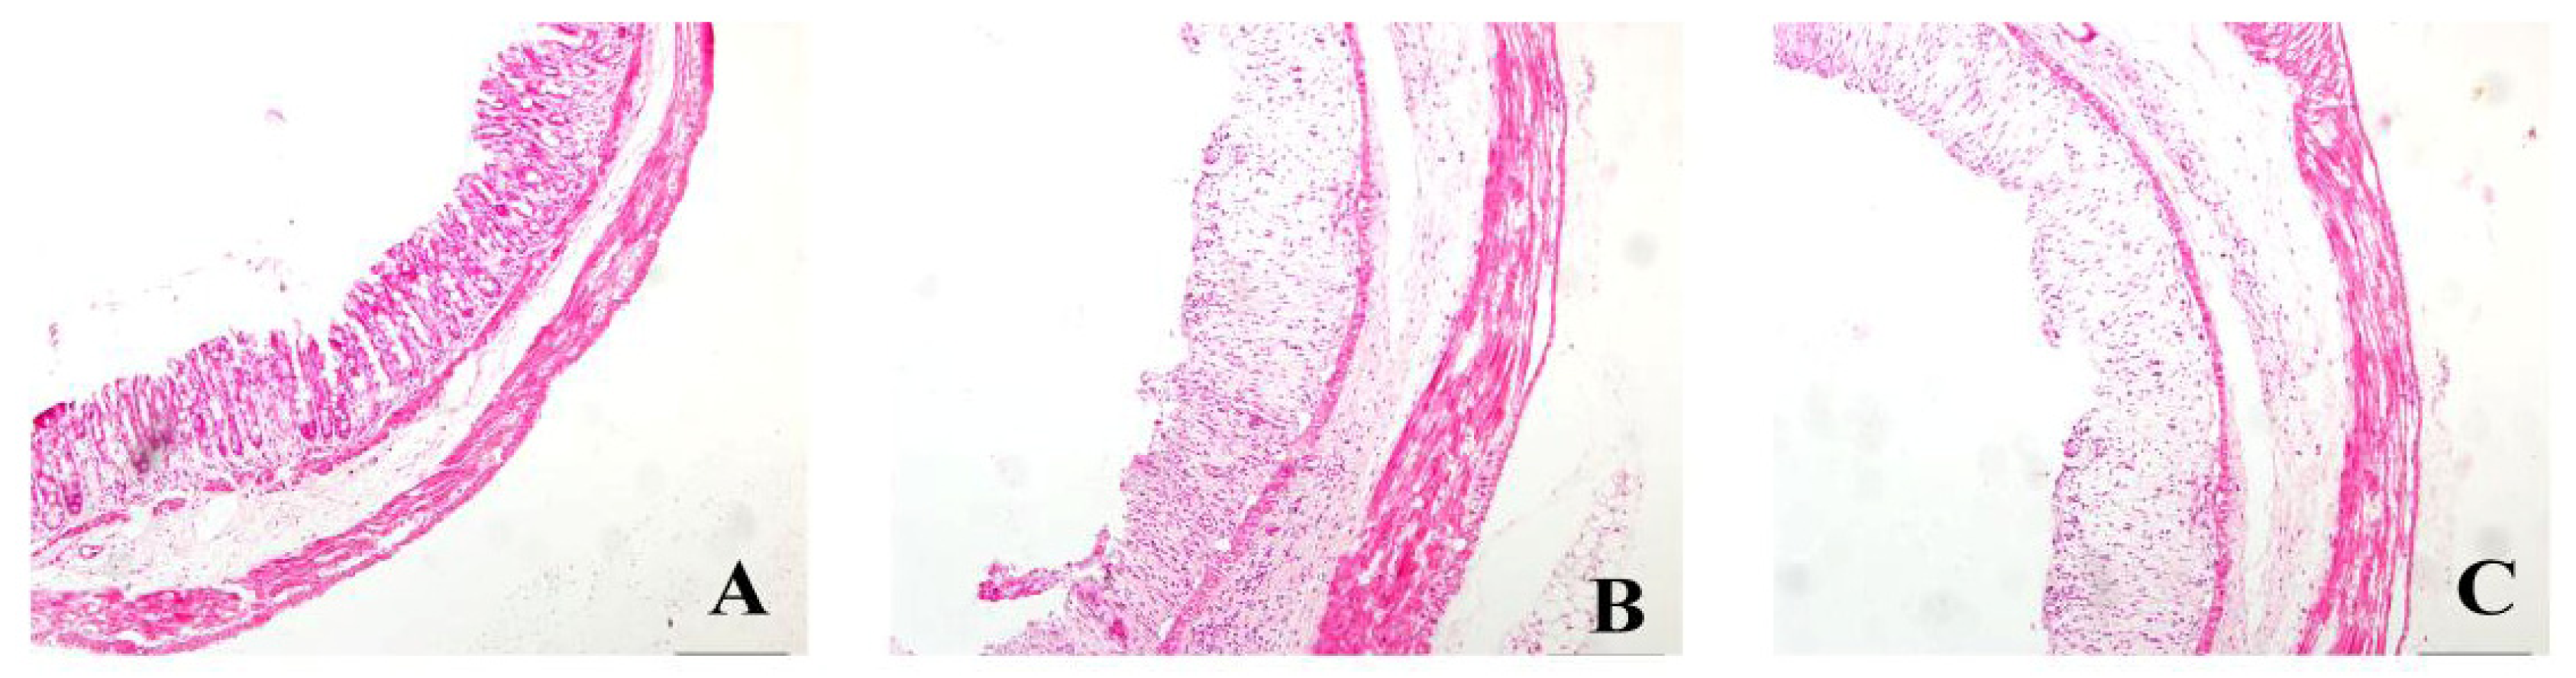

Histopathologic changes were assessed by HE stain (Figure 1). Colonic membrane structure was intact in the control group. Extensive lesions were observed in DSS group, including mucosa destruction, crypt destruction and glands separation. mesalazine group, VSL#3 group, heat-killed VSL#3 group and VSL#3 + mesalazine group had significantly less histological damage compared with DSS group. Heat-killed VSL#3 group have reduced mucosal injury in experimental colitis. There was no significant difference between heat-killed VSL#3 group and mesalazine group (p > 0.05) (Figure 2).

Figure 1.

HE staining of rat colonic tissue samples (×10) from the (A) control group and (B–G) rats treated with DSS and (C) normal saline; (D) mesalazine; (E) VSL#3; (F) heat-killed VSL#3; and (G) mesalazine plus VSL#3.